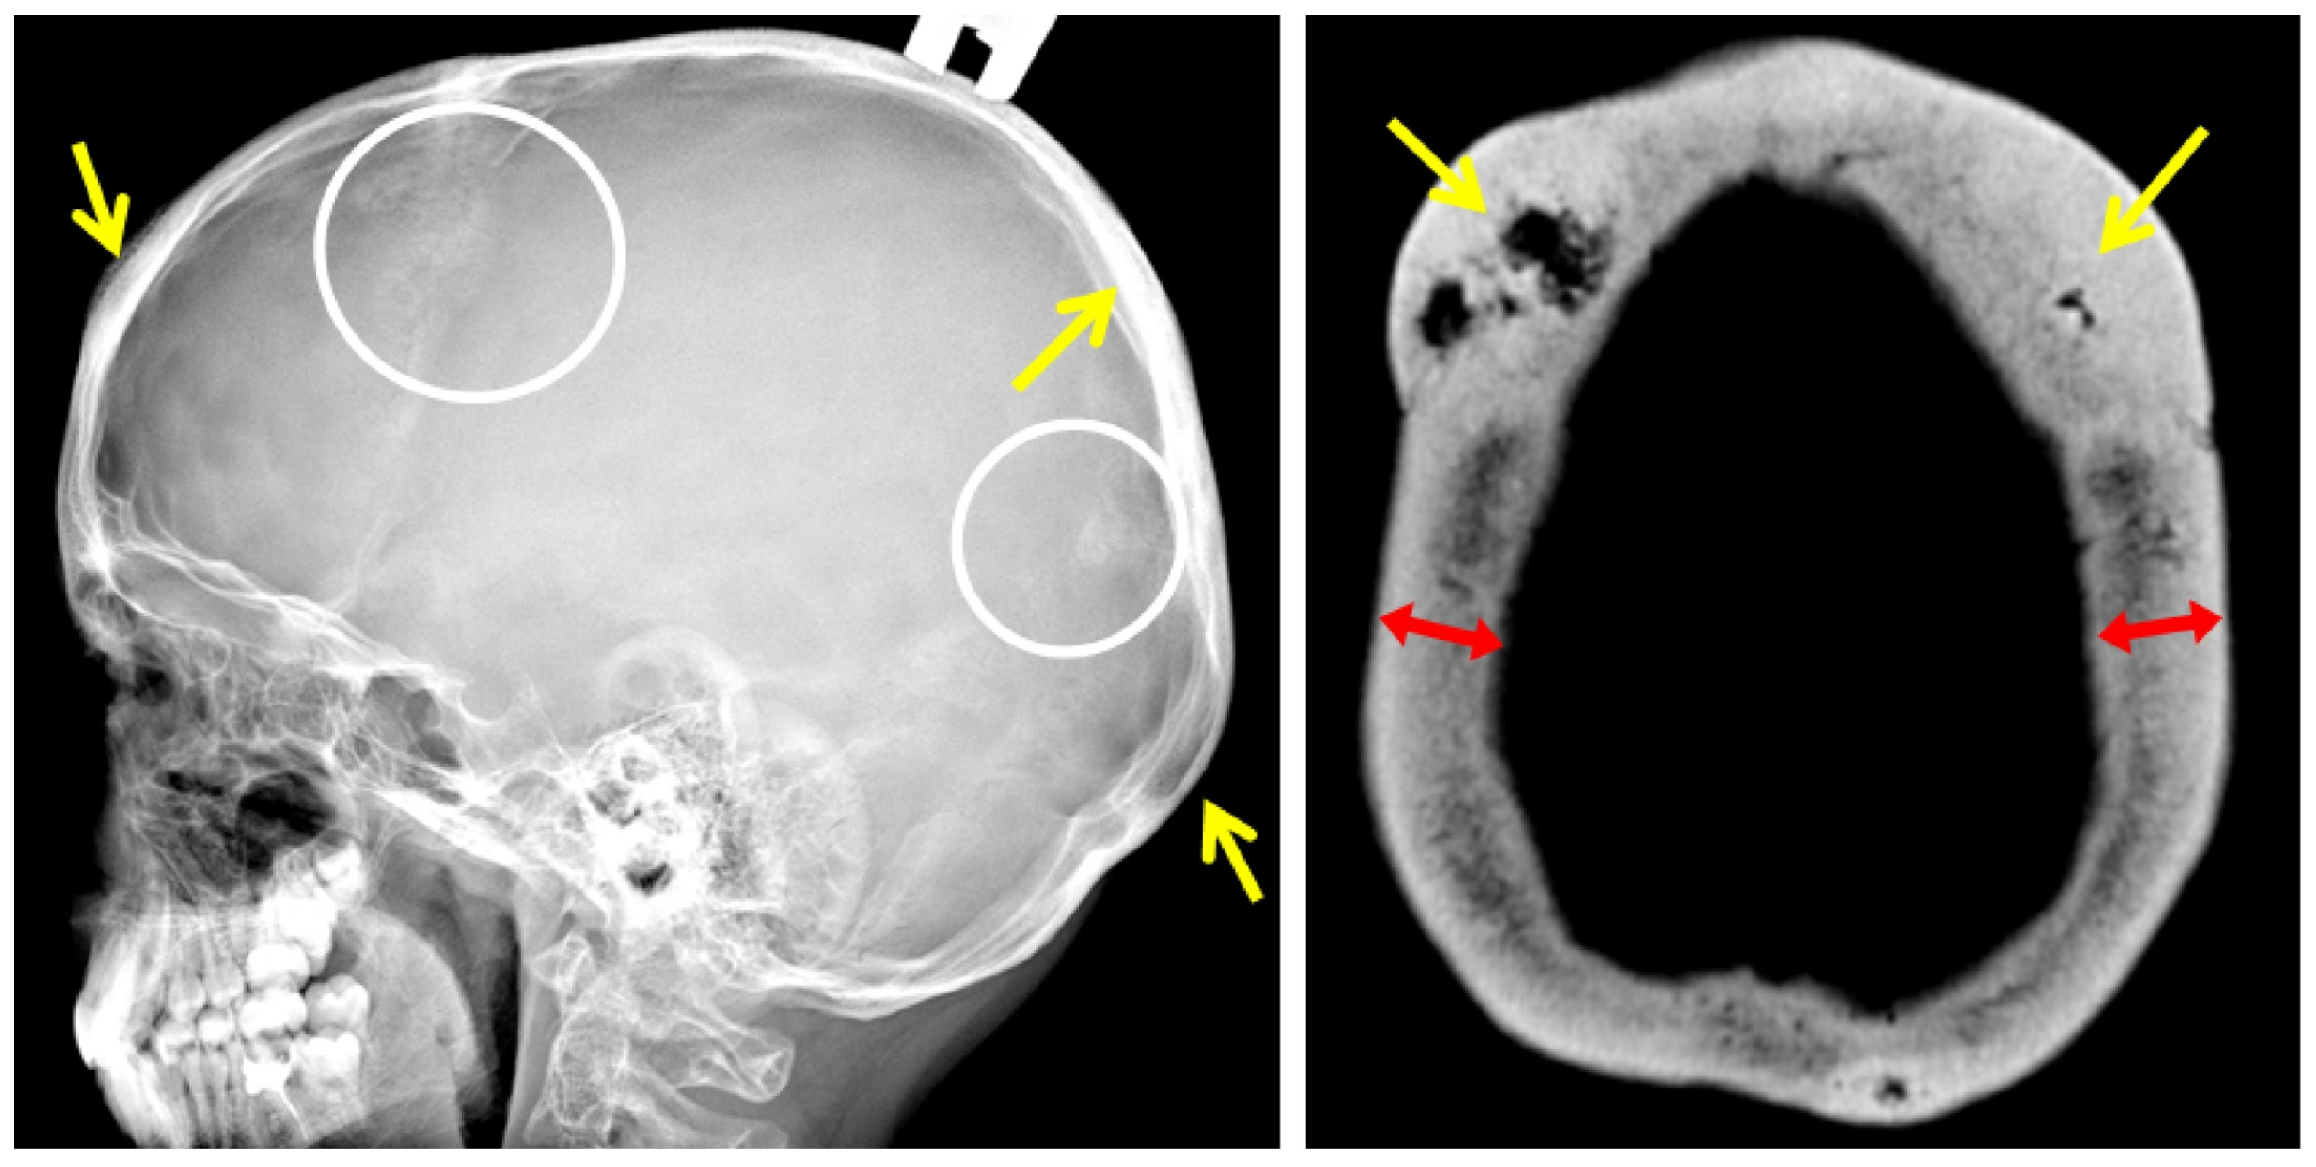

Examination of an 11-year-old proband and his uncle of the same age revealed bony prominences of the calvaria in the forehead area 3 × 3 cm in size. In the mother and grandmother of the proband, the same formations were found in the forehead area 5 × 5 cm in size and at the back of the head 3 × 3 cm in size (Figure 4). Sclerotic lesions of the skull bones were found in all family members during X-ray and CT examination of the skull (Figure 5).

A lateral radiograph of the scull performed at the age of 30 years revealed sclerotic lesions involving the frontal, parietal, and temporal bones with the maximum size in the projection of the coronal suture. These findings were confirmed by a CT scan of the skull bones.

The skull lesions are a fascinating feature of the disease, limited to the vault of the skull. Standard skull X-rays reveal multiple areas of bone involvement, with the appearance of ring-shaped formations resembling a doughnut, lytic lesions of the skull vault, and thickening of the skull vault and/or base. In some cases, sclerotic lesions of the skull bones lead to the protrusion of the outer plate of the skull vault, clinically manifested as a palpable thickening in this area of the head (Figure 4). Skull lesions often progress asymptomatically and are usually detected incidentally on computed tomography (CT) or magnetic resonance imaging (MRI) of the brain. Characteristic skull bone lesions can be diagnosed with standard X-rays, but CT and MRI, by detecting small formations in the diploic space of the skull, allow for early diagnosis of the disease in patients with only multiple fractures in the absence of clinically palpable subcutaneous thickening of the head. It should be noted that doughnut-shaped skull lesions are not observed in early childhood due to age-related structural peculiarities (the diploic space is not well developed in children) and can only be detected at a later age [9]. With age, the number and size of lesion foci increase. In addition, it is important to verify these bone lesions as a benign process and differentiate them from other lytic lesions of the skull vault (intradiploic epidermoid cysts, hemangiomas, eosinophilic granulomas, etc.), including malignant primary and metastatic lesions [1,10,11]. The detection of typical changes in the skull vault bones in combination with the patient’s age, family history, and clinical symptoms of the disease is of fundamental importance for differential diagnosis with osteogenesis imperfecta and for establishing the correct diagnosis.

Figure 5. Lateral radiograph of the skull (F2 III-2): sclerotic lesions (white circles) and thickening (yellow arrows) of the bones. Axial CT scan of the skull vault (F2 I-2): doughnut-shaped lesions (yellow arrows) and significant thickening of the cranial bones (red arrows).